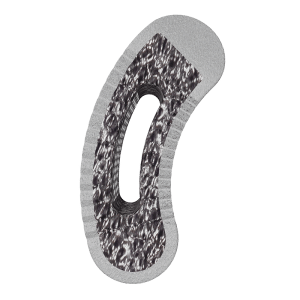

- Straight and pre-lordosed, titanium and cobalt chrome rods with hex or rounded ends and etched lines for rotational reference